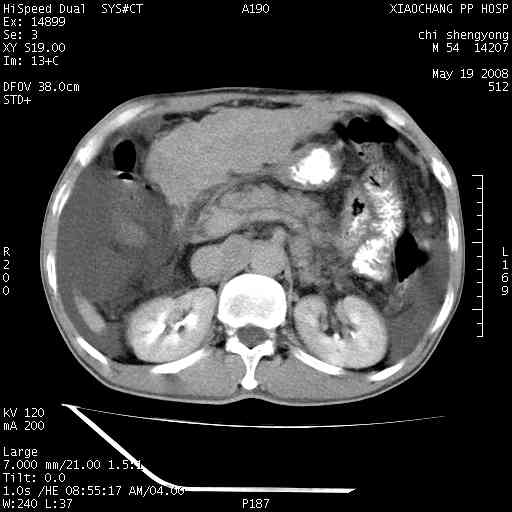

以下是引用zjzjr在2008-5-21 10:52:00的发言:[br]肝左叶巨块型肝癌伴门静脉左支瘤栓形成.肝硬化、腹水,胃底静脉曲张,脾术后改变。

以下是引用随光逐影在2008-5-21 16:20:00的发言:[br]1)肝左叶肝癌伴门静脉左支瘤栓形成,腹膜后淋巴结转移。2)肝硬化、腹水、胃底静脉曲张。3)胆囊炎。4)脾脏缺如,为切除术后所致。